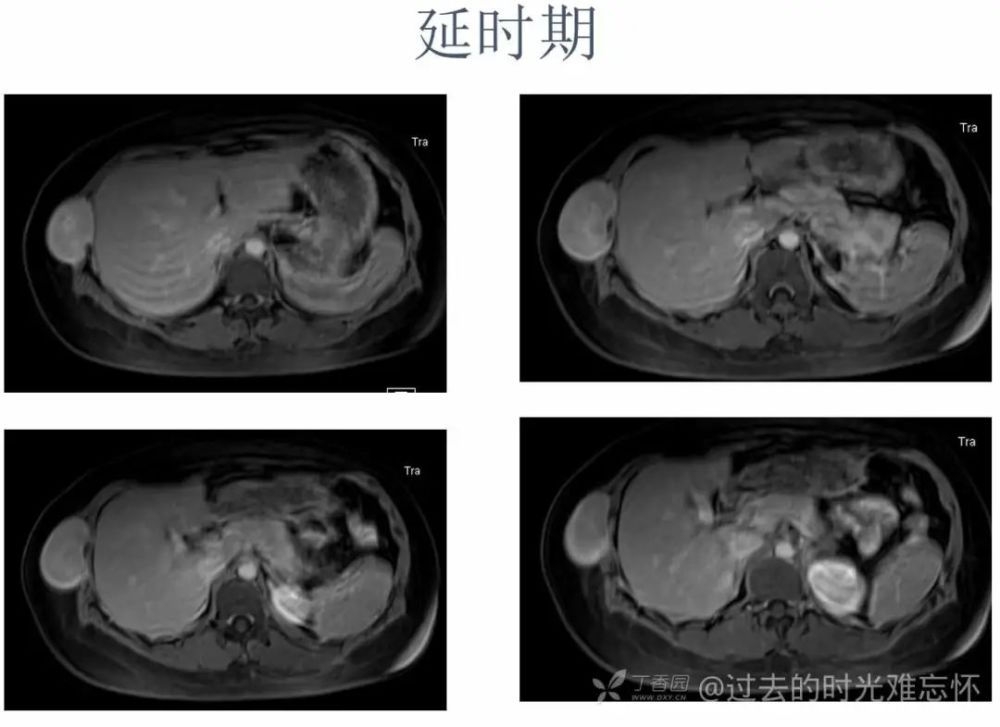

女,22 岁。右下侧胸壁疼痛、不适 10 年,近 3 年发现右侧腋中线近肋弓处肿块。体检:局部皮肤无红肿,肿块质中等偏硬,活动度欠佳,压痛( + ),无血管杂音。超声描述「低回声包块」。化验室指标无异常。